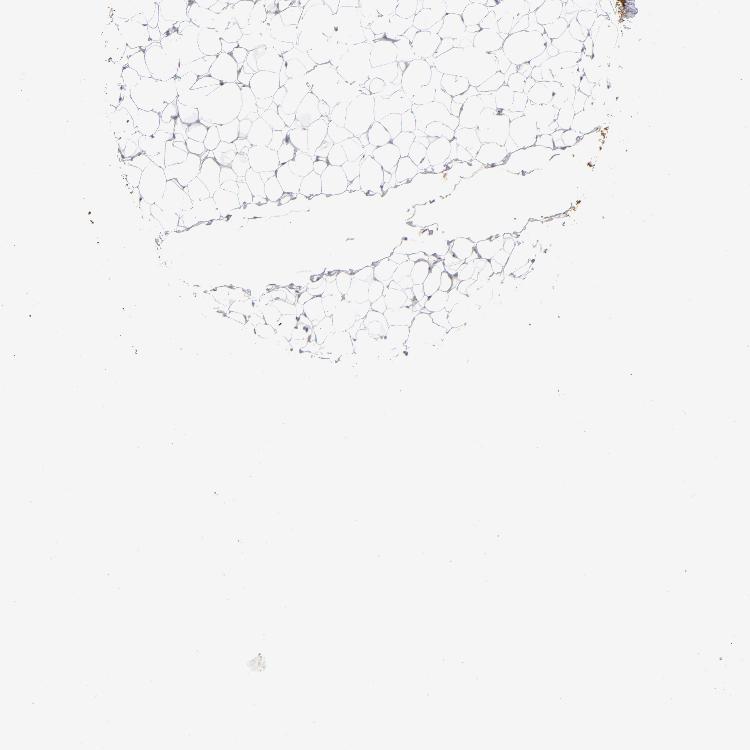

SOFT TISSUE 2 - Antibody stainingi

Antibody staining in the annotated cell types in the current human tissue is reported as not detected, low, medium, or high, based on conventional immunohistochemistry profiling in selected tissues. This score is based on the combination of the staining intensity and fraction of stained cells.

Each image is clickable and will lead to virtual microscopy that enables deeper exploration of all samples and also displays staining intensity scores, fraction scores and subcellular localization as well as patient and tissue information for each sample.

Antibody HPA002913

Fibroblasts Medium

Peripheral nerve Low